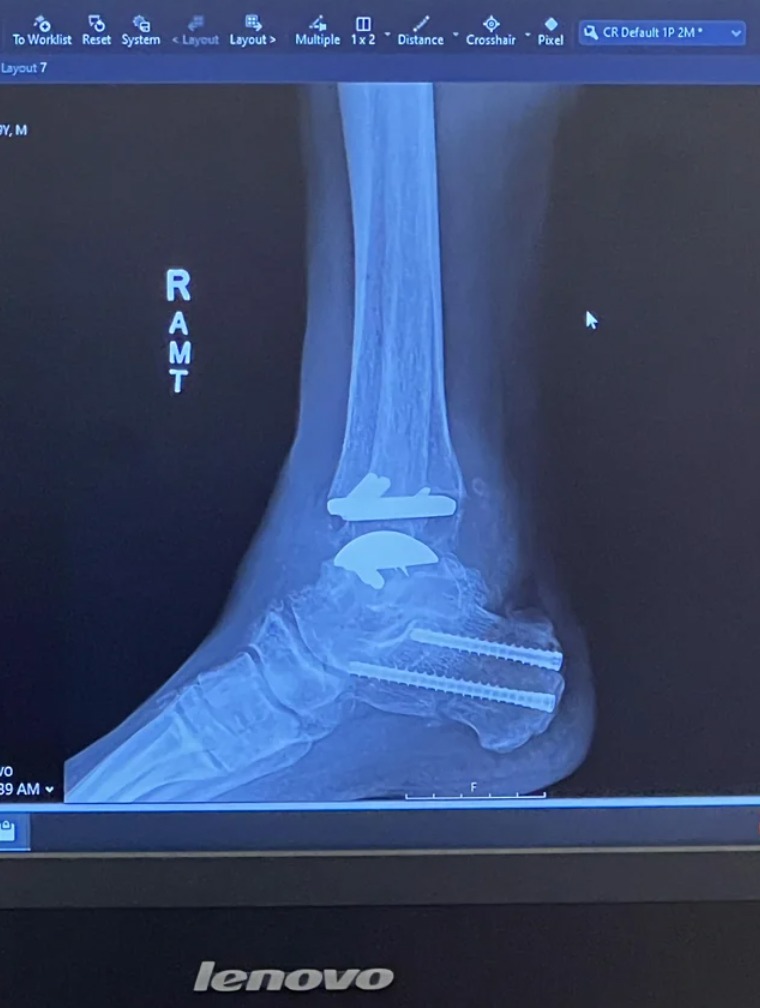

Môj umelý pravý členok s chirurgickými skrutkami v päte